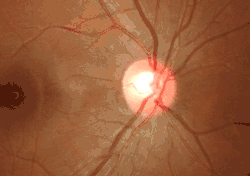

![]() Ophthalmoscopy photograph showing the optic disc as a bright area on the right where blood vessels converge. | |

The optic disc or optic nerve head is the point of exit for ganglion cell axons leaving the eye. Because there are no rods or cones overlying the optic disc, it corresponds to a small blind spot in each eye.

The ganglion cell axons form the optic nerve after they leave the eye. The optic disc represents the beginning of the optic nerve and is the point where the axons of retinal ganglion cells come together. The optic disc in a normal human eye carries 1–1.2 million afferent nerve fibers from the eye toward the brain. The optic disc is also the entry point for the major arteries that supply the retina with blood, and the exit point for the veins from the retina.[1]

The optic disc is placed 3 to 4 mm to the nasal side of the fovea. It is a vertical oval, with average dimensions of 1.76mm horizontally by 1.92mm vertically.[2] There is a central depression, of variable size, called the optic cup. This depression can be a variety of shapes from a shallow indentation to a bean pot—this shape can be significant for diagnosis of some retinal diseases.